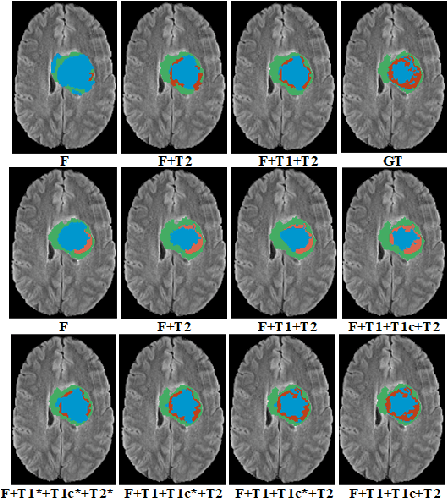

In large studies involving multi protocol Magnetic Resonance Imaging (MRI), it can occur to miss one or more sub-modalities for a given patient owing to poor quality (e.g. imaging artifacts), failed acquisitions, or hallway interrupted imaging examinations. In some cases, certain protocols are unavailable due to limited scan time or to retrospectively harmonise the imaging protocols of two independent studies. Missing image modalities pose a challenge to segmentation frameworks as complementary information contributed by the missing scans is then lost. In this paper, we propose a novel model, Multi-modal Gaussian Process Prior Variational Autoencoder (MGP-VAE), to impute one or more missing sub-modalities for a patient scan. MGP-VAE can leverage the Gaussian Process (GP) prior on the Variational Autoencoder (VAE) to utilize the subjects/patients and sub-modalities correlations. Instead of designing one network for each possible subset of present sub-modalities or using frameworks to mix feature maps, missing data can be generated from a single model based on all the available samples. We show the applicability of MGP-VAE on brain tumor segmentation where either, two, or three of four sub-modalities may be missing. Our experiments against competitive segmentation baselines with missing sub-modality on BraTS'19 dataset indicate the effectiveness of the MGP-VAE model for segmentation tasks.